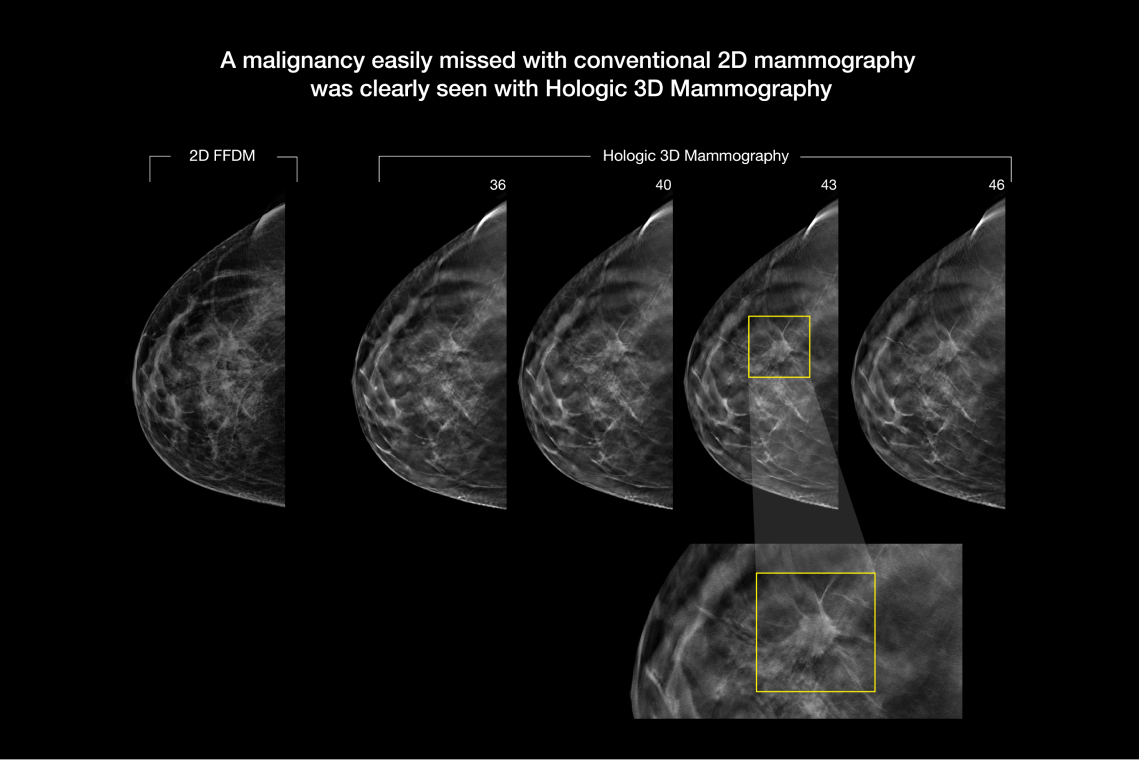

The Selenia Dimensions system's Genius 3D Mammography exam offers the only breast tomosynthesis technology with the following advantages over 2D mammography, proving that not all tomo is the same:

- Proven to detect 20%-65% more invasive breast cancers compared to 2D alone, an average increase of 41%.1

- FDA approved as superior for women with dense breasts compared to 2D alone.2,4

Hologic has further advanced breast cancer screening by producing 2D images from breast tomosynthesis data using C View software, resulting in a Low Dose Genius 3D Mammography exam with superior clinical performance compared with 2D alone.4

This Low Dose Genius 3D Mammography exam is performed in a rapid 3.7 second scan time for greater patient comfort and low patient dose, due to the elimination of 2D X ray exposures. The synthetic 2D images and 3D slices are reviewed together to make clinical decisions or diagnoses part of the Genius 3D Mammography screening exam.